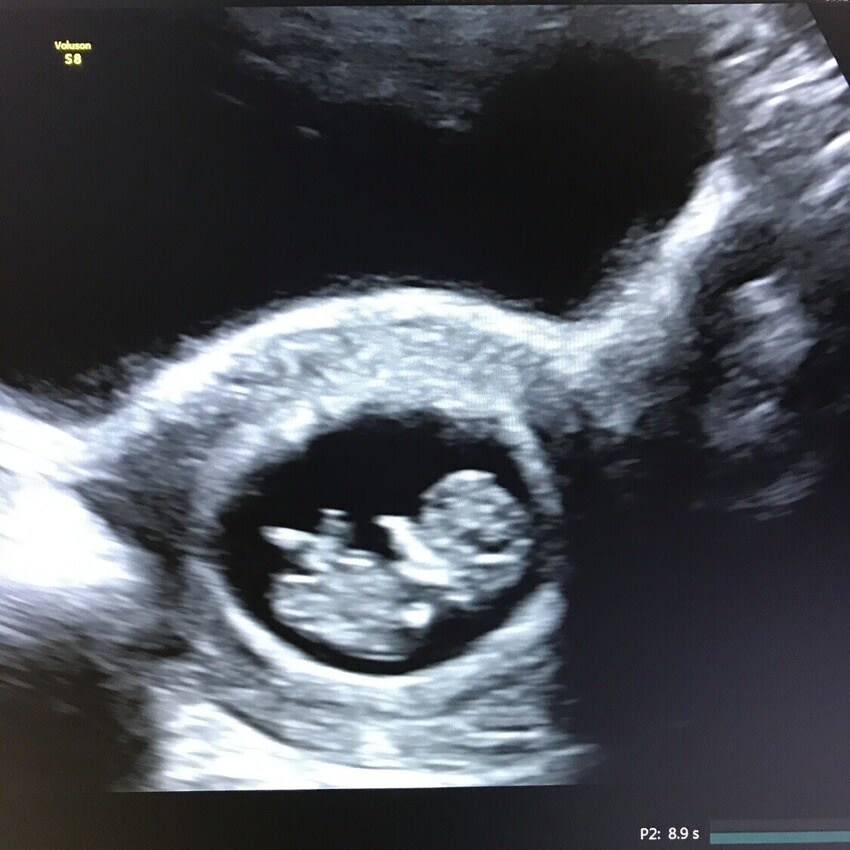

Verify that the pregnancy is present. early pregnancy ultrasound has several goals, including: trouvez rapidement un spécialiste en tep scan à france ou un soignant proposant des actes de pet scan. • être à jeun 6 heures avant l’examen (vous pouvez boire,. tep petscan fdg de viabilité cardiaque. it can be coupled with a kind of radar to study vessels; le centre de médecine nucléaire et tep paris nord, l’un des principaux centres du val d’oise, s’adresse aux patients envoyés. We offer you a diagnosis made by experts working. retrouvez la liste de toutes les tep scan dans les plus grandes villes de france.